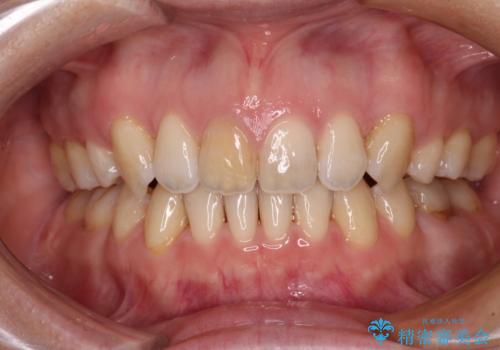

上下の前歯に隙間が空くほど上顎前歯が前に飛び出していましたが、抜歯矯正により上下前歯がぴったりと付くほど口元を引っ込めることができました。

上顎左右第一小臼歯2本、下顎左右第二小臼歯2本を抜歯し、ワイヤー装置にて口元を引っ込めるよう矯正治療を行うこととしました。